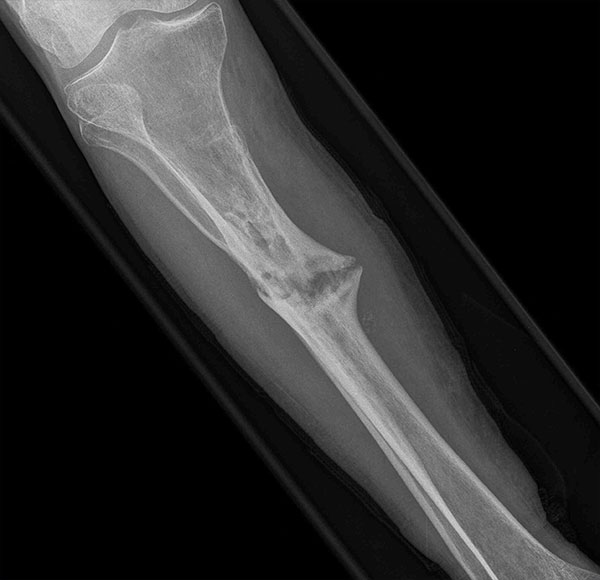

- Focus Area Reconstructive Surgery & Non-Surgical Management to Improve Bone Healing

- Primary Objective Observational outcome study of peripheral nerve repair and reconstruction